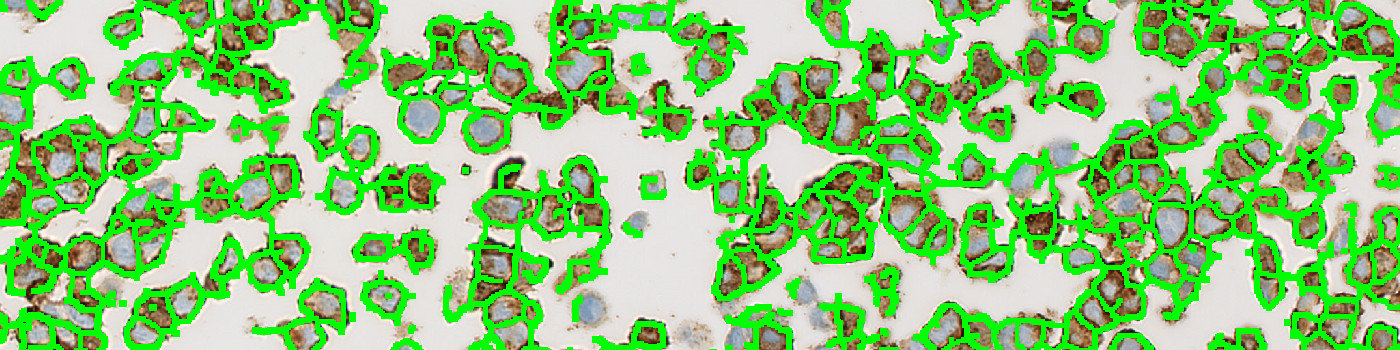

Raw image of cell line cores with different HEr2 expression.

This APP can be used for quality control of HER2 negative (i.e. 0), 1+, 2+ and 3+ cell line material to ensure that each cell line block complies with the expected HER2 expression before the material is used as reference standard for IHC assays. The APP quantifies the HER2 expression in each cell line core and relates this expression to a known reference value for each cell line expression level.

First, a pre-processing step identifies the stained membrane pixels that contribute to linear structures in the image. Then, segmentation rules are employed identifying the membrane segments in the image. The segmentation is based on the intensity of brown in the pixels and the correct dimensions of linearity. After identifying pixels that constitute to brown linear structures and make up part of a membrane segment, post-processing steps are employed. The post-processing steps are used to skeletonize the membrane, removing small membrane fragments and merging membrane fragments which are not perfectly connected. From the membrane fragments remaining after post-processing, the connectivity can be calculated. Finally, the connectivity is translated into a classical HER2 score of 0, 1+, 2+ or 3+ based on known connectivity reference values for HER2 cell line cores expressing a score of either 0, 1+, 2+ or 3+.